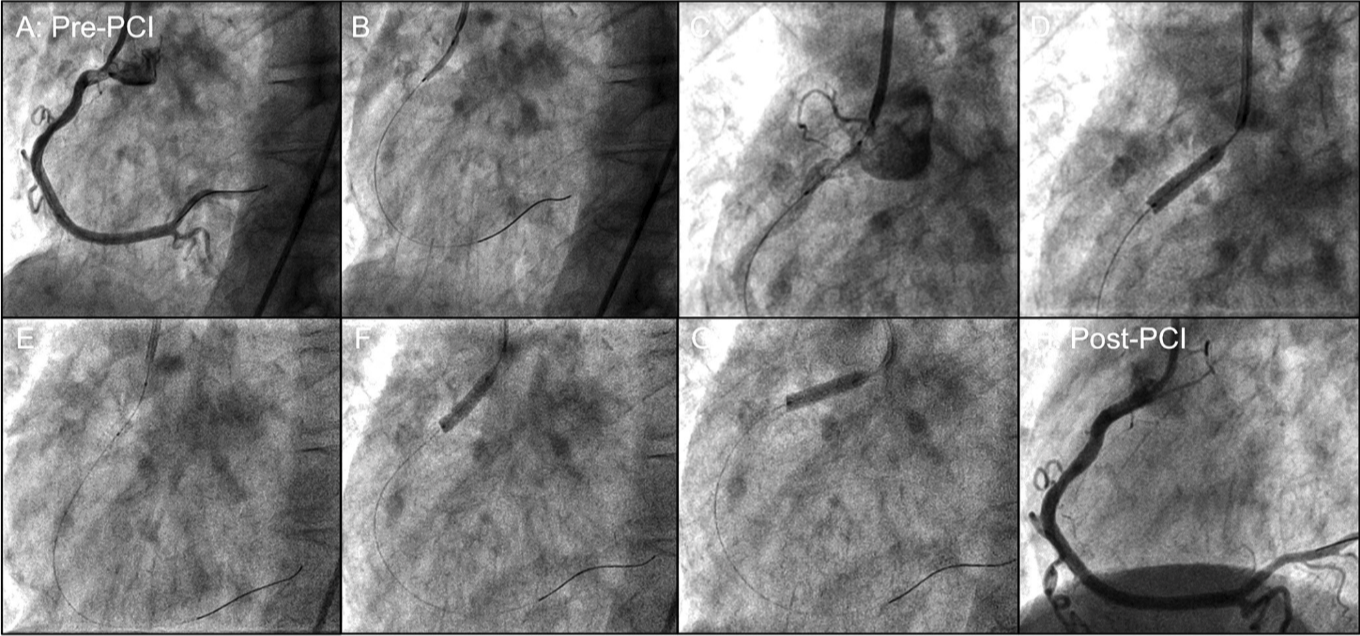

The third joystick for guide-catheter manipulation was used during multiple procedures, as it allowed for improved engagement of the target coronary, especially if it became disengaged during the intervention. It also enabled ostial coronary stenting and flaring of the stent robotically as necessary (Figure 3).